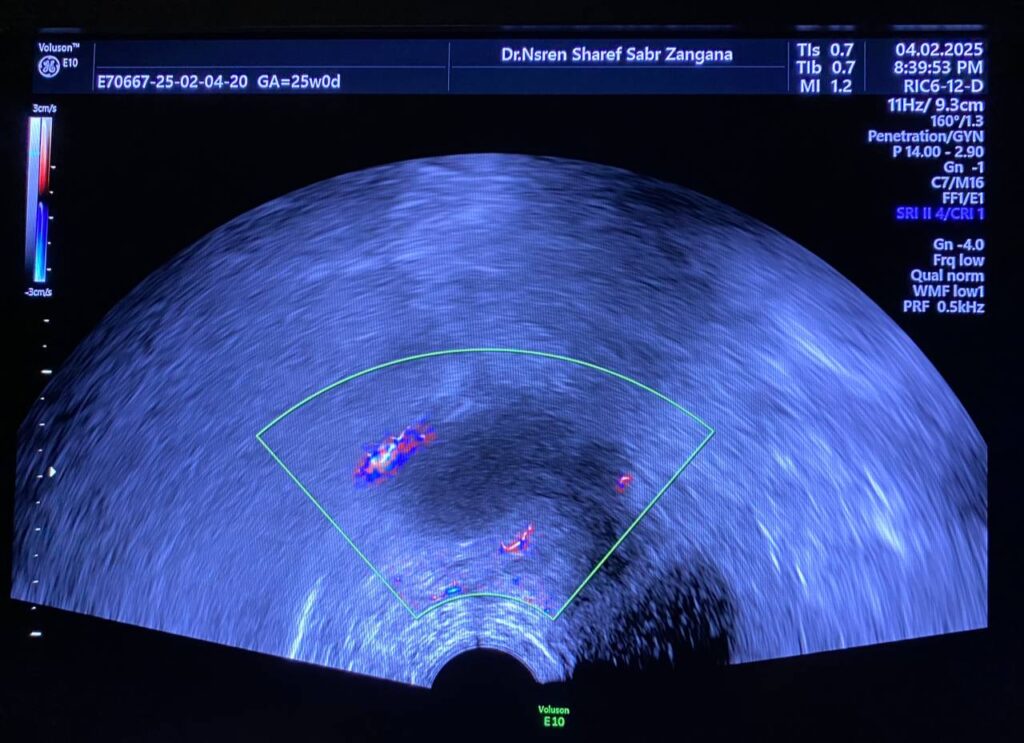

Bulky uterus, endometrial lining thickness 2mm, occupied by clear avascular fluid , mostly due to mass effect , Presence of hypoechoic solid mass 68x48mm ,vascular on color Doppler , Color Score 4 (Hyper vascular) , within right sided posterior submucosal subserosal region , associated with other two smaller masses seen on the anterior wall , their sizes are 19x18mm& 8x12mm (Metastasis? Lymphoma ??) or other suspicious masses